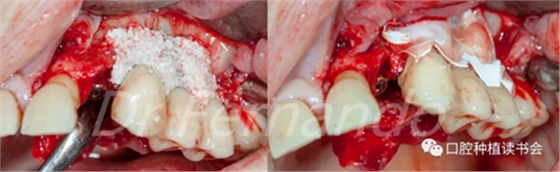

在無菌容器中將Cerasorb ?M(科盧森)骨粉與哌拉西林-他唑巴坦透明質(zhì)酸鈉溶液混合,將骨粉放置在缺損處,并用預(yù)先浸泡過哌拉西林-他唑巴坦透明質(zhì)酸鈉溶液的膠原膜覆蓋該區(qū)域并進行縫和(圖15、圖16 )。

圖15 種植體周圍骨缺損區(qū)植骨+覆蓋可吸收膜

在骨粉上方覆蓋 Osgide? 可吸收膠原膜(Curasan?-科盧森) ,用絲線嚴密關(guān)閉傷口(圖 22 )

圖22 植骨區(qū)覆蓋可吸收膠原膜,關(guān)閉創(chuàng)口